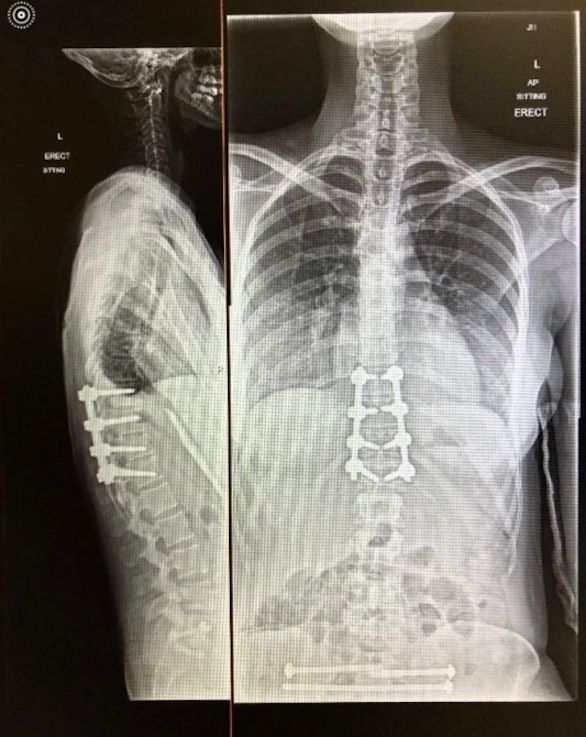

في المستشفى، كان الأطباء قلقين من أنها لن تمشي مرة أخرى بسبب شدة إصاباتها، حيث كُسر ظهرها وحوضها وساقاها وتحطم كاحلها في 30 مكاناً. ولكن لحسن الحظ، بعد 12 أسبوعاً فقط من الحادث، بدأت صوفي خطواتها الأولى في منزلها.